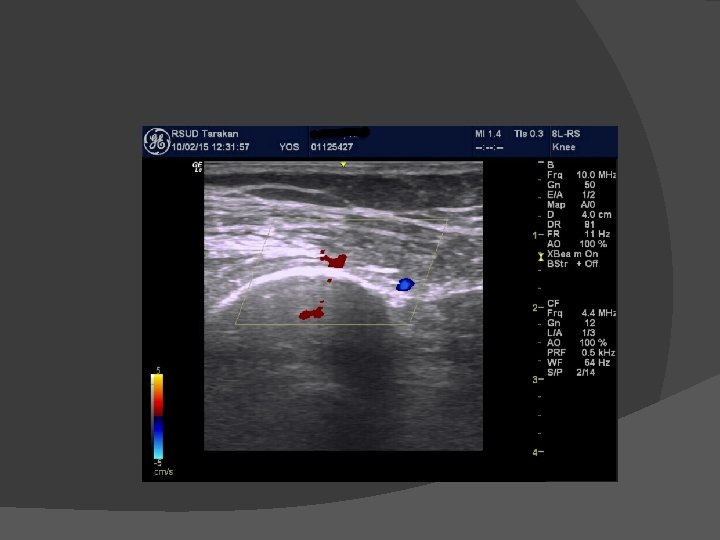

Osteoarthritis Pain � nyeri pada lutut � nyeri bertambah jika beraktifitas � lutut berbunyi � gangguan gerak aktif dan pasif

Genicular neurolysis

USG

� Kasus 5 Wanita, 67 tahun, mengeluh nyeri sendi lutut kanan sejak 2 tahun. Di diagnosis osteoarthritis grade 3 dan dianjurkan untuk operasi Total knee replacement namun menolak. Genicular nerve neurolysis